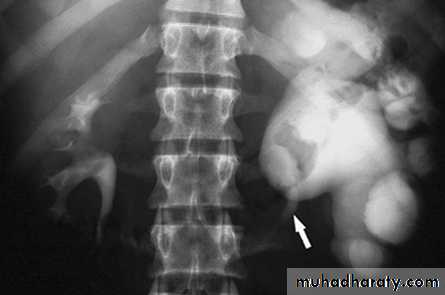

CALCULIMost renal stones are calcified and show varying density on plain x-ray films.

Pure uric acid & xanthine stones are radiolucent on plain radiography, but are well seen at CT or US.

Plain film is more sensitive than US for detecting ureteric calculi.

Stones regardless their composition are intensely echogenic (By U/S) and cast acoustic shadows